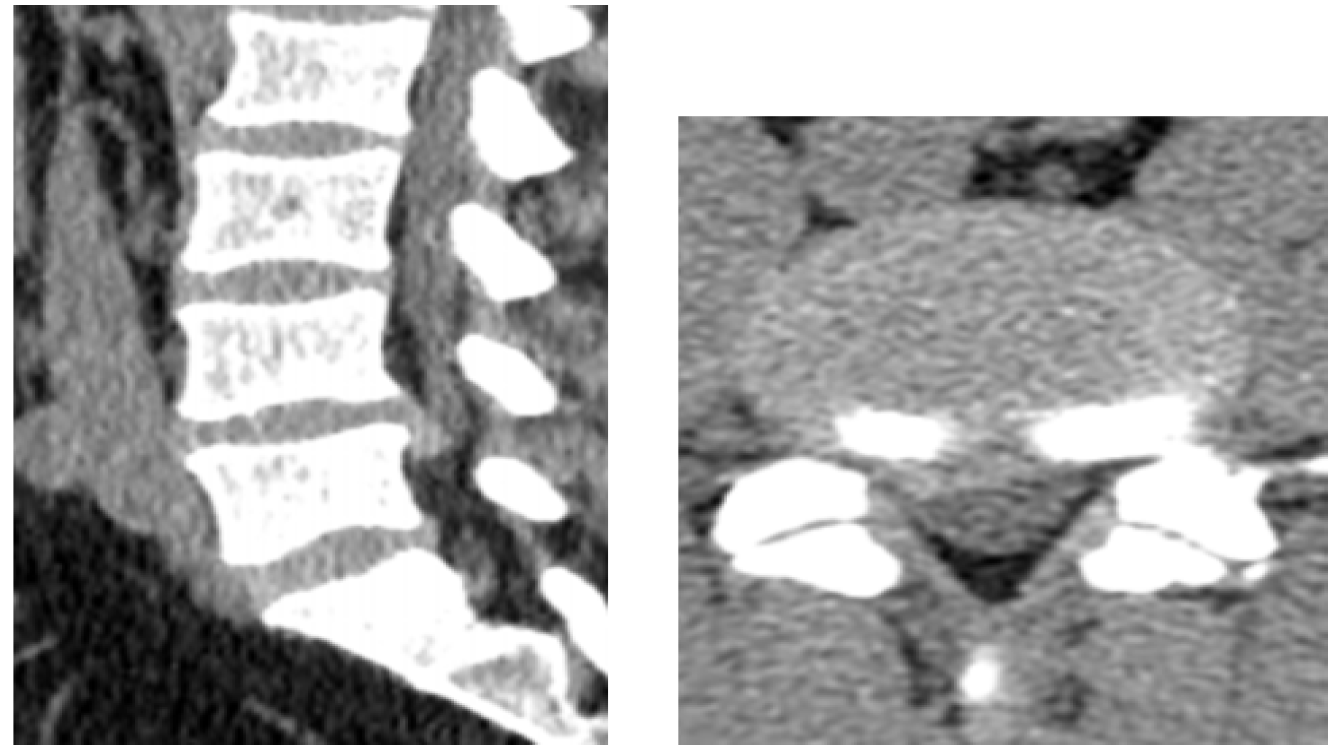

The definition of giant Lumbar Disc Herniation (GLDH) varies among different authors. It includes a herniation affecting more than 8mm, 33%, 40%, 50%, or 75% of the sagittal diameter of the spinal canal, or herniation causing complete spinal canal stenosis [3,10,11]. Our study defined GLDH as a herniated disc that affects more than 50% of the sagittal diameter of the spinal canal (Figure 1,2). Giant lumbar disc herniations are rare than more minor herniations [1]. Therefore, the incidence of GLDH in our study (4.3%) is inferior to the incidence in the literature: 8 to 22% [1,11-13].

Figure 2: Sagittal (Left) and Axial (Right)CT Scan Showing a Giant Right Posterolateral Lumbar Disc Herniation at L4L5 Level Migrated Down